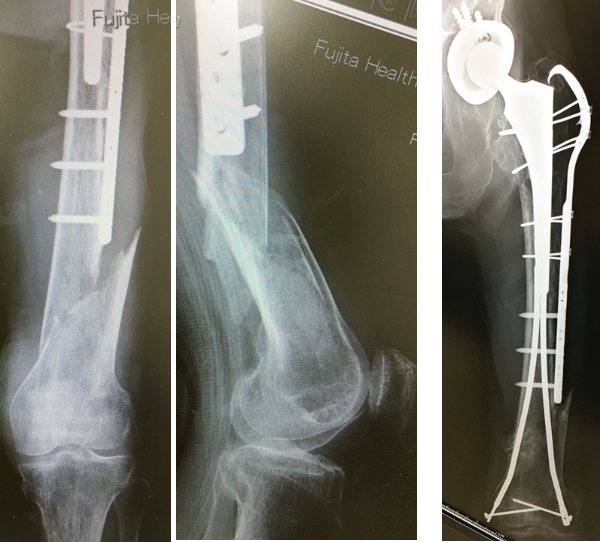

TKAはおもにOA(図2,3)やRA(図4)、UKAは骨壊死(図5)やOAの内側罹患例に行います。左右罹患例には両膝同日手術も施行しています(図3)。手術の目的は除痛、膝関節機能の回復によるADL、QOLの改善です。

人工膝関節は多機種ありますが、当科では自家組織(骨や靭帯)温存に配慮して、主に前十字靭帯のみ切除するCR型を選択し、膝蓋骨は非置換、セメントレス用コンポーネントを用いています(図2)。後療法は両側例でも翌日から離床と荷重を許可し、入院加療は約2週間です。

図4 RAに対するTKA

図5 大腿骨内側顆部骨壊死に対するUKA